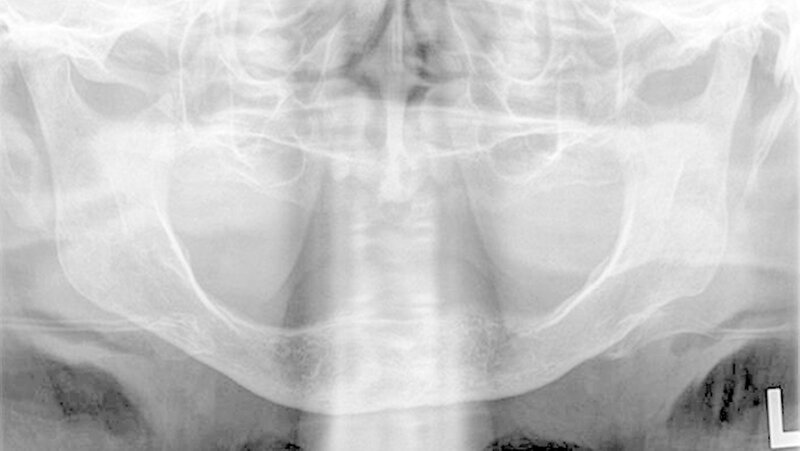

Die klinische Untersuchung zeigte eine überwärmte, schmerzhafte Schwellung präauriculär links und eine stark eingeschränkte Mundöffnung bei zahnlosem Kiefer. Das angefertigte Orthopantomogramm und die Schädelaufnahme in posterior-anteriorer Projektion gaben keinen eindeutigen Hinweis auf Pathologien im Bereich des linken Kiefergelenks, mit denen die ausgeprägten Beschwerden der Patientin hätten erklärt werden können.

Es war lediglich ein stark verschmälerter Gelenkspalt im Bereich des linken Kiefergelenks erkennbar, woraufhin eine Computertomografie des Unterkiefers durchgeführt wurde (Abbildungen 1 und 2). Dabei zeigten sich eine Deformierung des linken Kiefergelenksköpfchens mit Unregelmäßigkeiten der Kortikalis sowie eine Fremdkörpereinlagerung (freie Gelenkkörperchen) im Bereich des Gelenkspalts (Abbildungen 3 und 4).